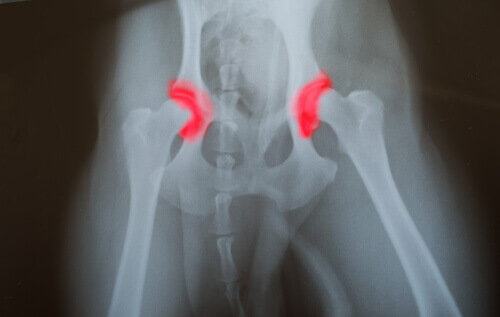

A displasia do quadril ou do cotovelo é uma doença que passa de geração em geração. Ocorre quando os ossos que formam uma articulação, do quadril ou do cotovelo, não estão encaixados ou alinhados corretamente.

Isso faz com que eles rocem um no outro e tenham movimentos inadequados, acelerando o desgaste. Essa condição leva a outros problemas resultantes do mau funcionamento da articulação. Entretanto, o grande problema é que essa doença é silenciosa.